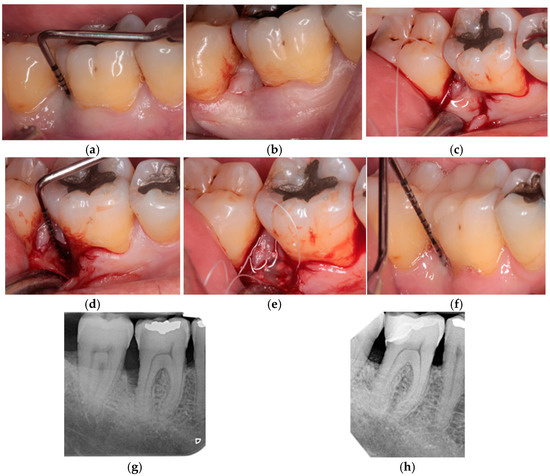

2. Materials and Methods

2.1. Design of This Study

3.2. Clinical and Radiographic Results